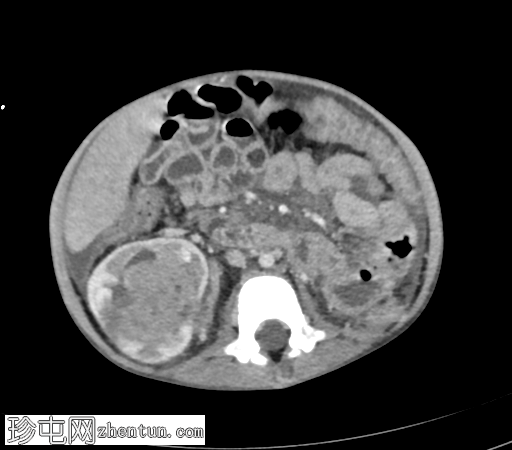

轴位增强扫描(门静脉期)

右肾极间区可见一巨大异质性肿块,伴坏死区域。

病灶延伸至扩张的右肾静脉、右下腔静脉和右心房。

轻至中度腹水。

可见亚厘米级腹主动脉旁淋巴结。

右侧少量胸腔积液,右下叶可见一小块强化胸膜下结节。

影像学特征提示右肾母细胞瘤(Wilms瘤),伴肿瘤血栓形成至下腔静脉和右心房。